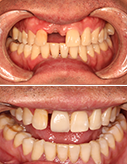

21个月牙套毕业,完美

上下牙齿不齐隐形矫正案例